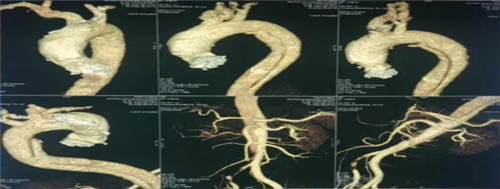

患者,男性42岁,患高血压数年,常年在外务工,以“突发剧烈背痛”在当地医院就诊并行胸部CT平扫及胸主动脉血管成像检查,CTA提示主动脉夹层、破口位于左锁骨下动脉远端,诊断为主动脉夹层,患者家属电话与乐鱼手机站入口介入科李建国主任联系,由当地120转入我院,患者胸背部剧烈疼痛、情绪血压极不稳定,随时有破裂死亡风险,命悬一线。李建国主任反复叮嘱,在转院途中务必控制好心率、血压。

经过紧锣密鼓准备,于2018年6月3日为患者在局麻下成功施行了介入胸主动脉夹层覆膜支架腔内修复术。